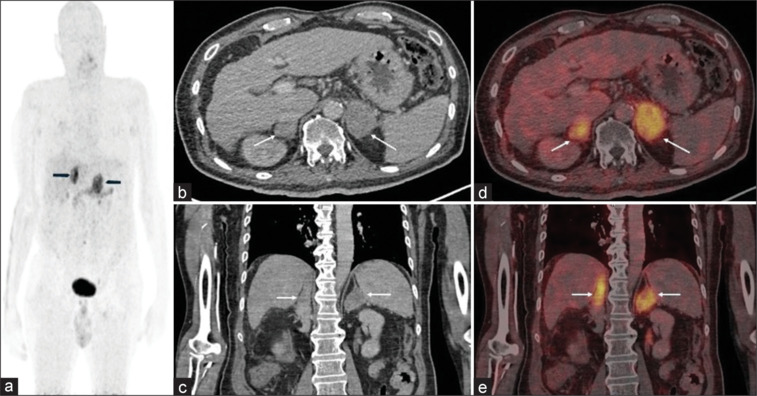

A 77-year-old male presented with pyrexia of unknown origin. Chest computed tomography (CT) showed adrenal lesions, a suspicion of neoplasia was raised, and Fluorodeoxyglucose Positron Emission Tomography (FDG PET-CT) was recommended. Since the patient had uncontrolled diabetes (Fasting Blood Sugar - 326 mg/dL), FDG-PET was not feasible. The patient, therefore, underwent Ga68-Fibroblast Activating Protein Inhibitor - 46 PET-CT (FAPI PET-CT). Scan showed high-grade Fibroblast Activating Protein (FAP) expression in bilateral enlarged adrenals. Findings appeared atypical for malignancy and the possibility of chronic inflammatory/infectious condition was raised. Biopsy proved adrenal histoplasmosis (AH). Although FDG avidity in AH is known and previously reported, this is best to our knowledge the first literature documentation of FAP expression in AH.